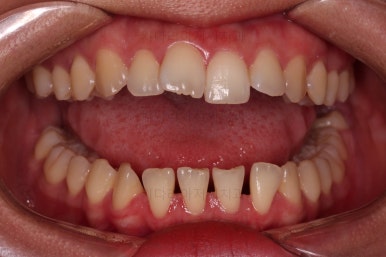

이제 부산치아교정 전후 비교를 해볼게요.

틈새가 예쁘게 모아졌고요.

교합도 좋아졌고, 앞니도 가지런해졌네요.

당연히 얼굴 모습도 마이너스 없이 예쁘게 마무리가 잘 되었습니다.